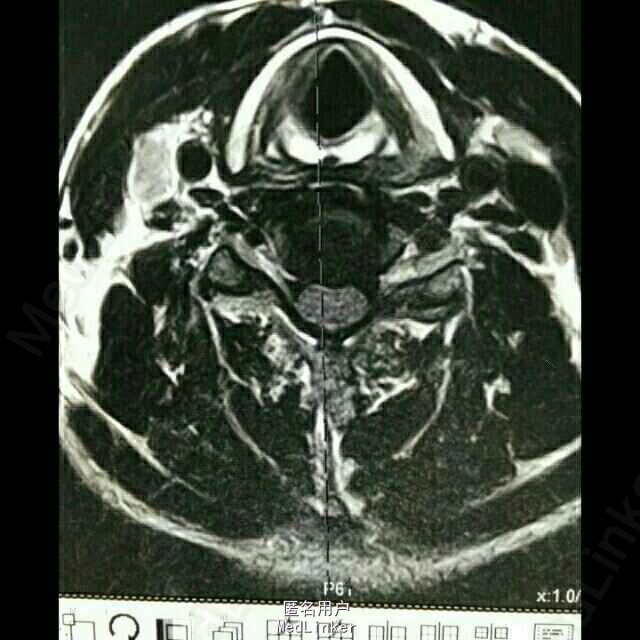

患者,男,59岁。20天前,患者无明显诱因出现右腿麻木,时有头晕、头痛、恶心等症状,亦未做过任何治疗,经休息后上述症状可缓解;在此期间,右下肢麻木逐渐加重,自觉行走无力。

脊柱序列如常,生理曲度存在,未见后凸及侧弯畸形。颈椎前屈、后伸、侧屈及旋转功能无明显受限,颈3-7椎间隙及棘突旁压痛。腰椎棘突及椎旁压痛,右小腿内侧皮肤感觉较左侧减退。